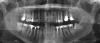

zebrka Опубликовано 9 октября, 2009 Поделиться Опубликовано 9 октября, 2009 (изменено) Уважаемые врачи! Посмотрите пож. снимок, мне очень нужно знать ваше мнение о качестве работы по протезированию верхних 7, 6, 7. Спасибо. Изменено 9 октября, 2009 пользователем zebrka Ссылка на комментарий

Bier Опубликовано 10 октября, 2009 Поделиться Опубликовано 10 октября, 2009 вкладка в 26 меня смущает. А коронки то вам сделали? Временные есть или нет никаких пока? Ссылка на комментарий

zybnaya feya Опубликовано 10 октября, 2009 Поделиться Опубликовано 10 октября, 2009 26 - это 6-ой?Временные да, поставили. А на правой 7-ке уже и постоянная стоит..Отличная подготовка к протезированию каналов. Что вас насторожило в протезировании? Временные коронки есть-это замечательно. Вкладки тоже нормально стоят Ссылка на комментарий

коляныч Опубликовано 12 октября, 2009 Поделиться Опубликовано 12 октября, 2009 А по моем тоже всё окей.в 2.6м 4 канала,3х штифтовая вкладка .всё о.к! Ссылка на комментарий